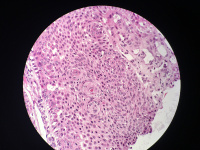

女性,鼻背部肿物3年,活检直径0.5厘米,

• 图3

考虑皮肤鲍温病

刺激性脂溢性角化病

高分化鳞癌

考虑鲍温氏病。

反转性毛囊角化病

激惹型脂溢性角化病。

日光性角化病